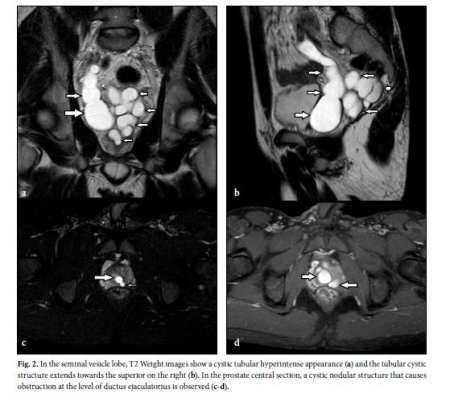

Zinner Syndrome (ZS) and Herlyn-Werner-Wunderlich Syndrome (HWWS) are congenital genitourinary anomalies accompanied by ipsilateral renal agenesis. These syndromes, which can cause symptoms such as infertility, pelvic pain, and bladder irritation, can be diagnosed by digital rectal examination, transrectal and abdominal ultrasonography (US), Computer Tomography (CT) and more ideally Magnetic resonance imaging (MRI). Similar physiopathological processes are observed in both syndromes and urogenital malformations accompany renal agenesis. We aimed to discuss the three cases of ZS in men and two HWWS  cases in women, which are rarely observed in the literature.